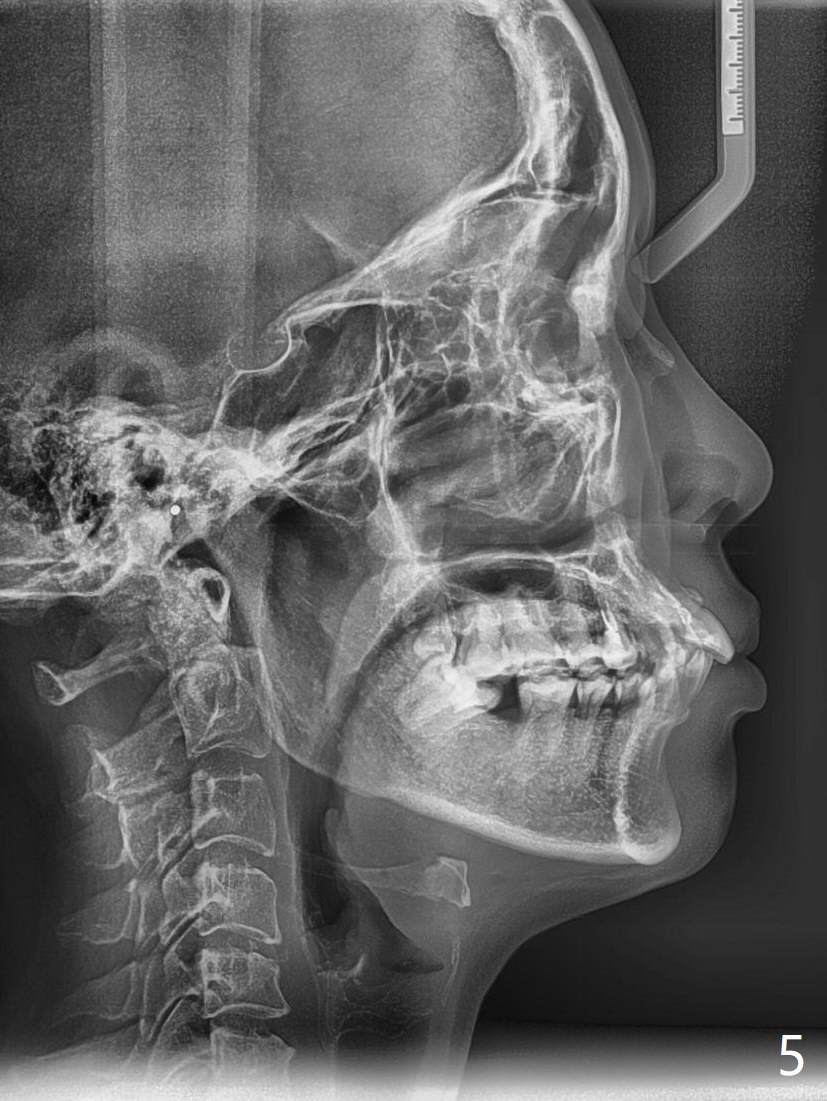

A 41-year-old woman requests ortho, bleach and replacement of 2 lower molars (L7s). The lips are protrusive (Fig.1,3), which is seemingly due to the underlying protrusive anterior teeth (Fig.4,5). Cephalometric tracing shows that SNA and SNB are both 87º (Fig.12), suggesting extraction. When the protrusive teeth are distalized, pay attention to move the upper dental midline to the right (Fig.2). BWs show subgingival calculus. SRP is required. Internal bleaching will be conducted for UL1 (Fig.7,11). Distalization is accomplished with extraction of 2 upper 1st bicuspids and using L8s as anchors so that no implants will be necessary for L7s. But the patient would rather have 2 of the lower 2nd molars for mastication. It appears that extraction of 4 bicuspids is pending (Fig.6-11). Supraeruption of U7s (Fig.6,8 arrows) will be corrected with banding.